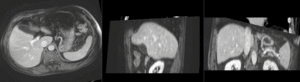

nonrigid registered MRI & CT

Color overlay of registered MRI onto CT, illustrating the fusion: MRI soft tissue contrast shows substructures & vasculature invisible on the CT